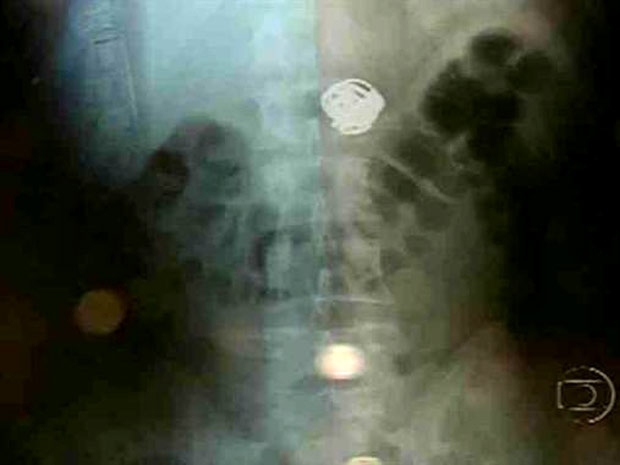

Assaltante engole joias e passa por cirurgia em Pernambuco; vídeo

Um dos criminosos envolvidos no roubo a moradores de um prédio na Praia de Piedade, na última quarta-feira (26), precisou ser levado ao Hospital Miguel Arraes, no Recife, após se queixar de um mal estar. Examinado, os médicos constataram que ele tinha engolido as joias. O rapaz, de 26 anos, estava preso no Centro de Triagem de Abreu e Lima (Cotel), quando precisou ser transferido para o hospital, neste domingo (30). Ele foi internado e as peças foram retiradas durante um procedimento cirúrgico na tarde desta segunda-feira (31).